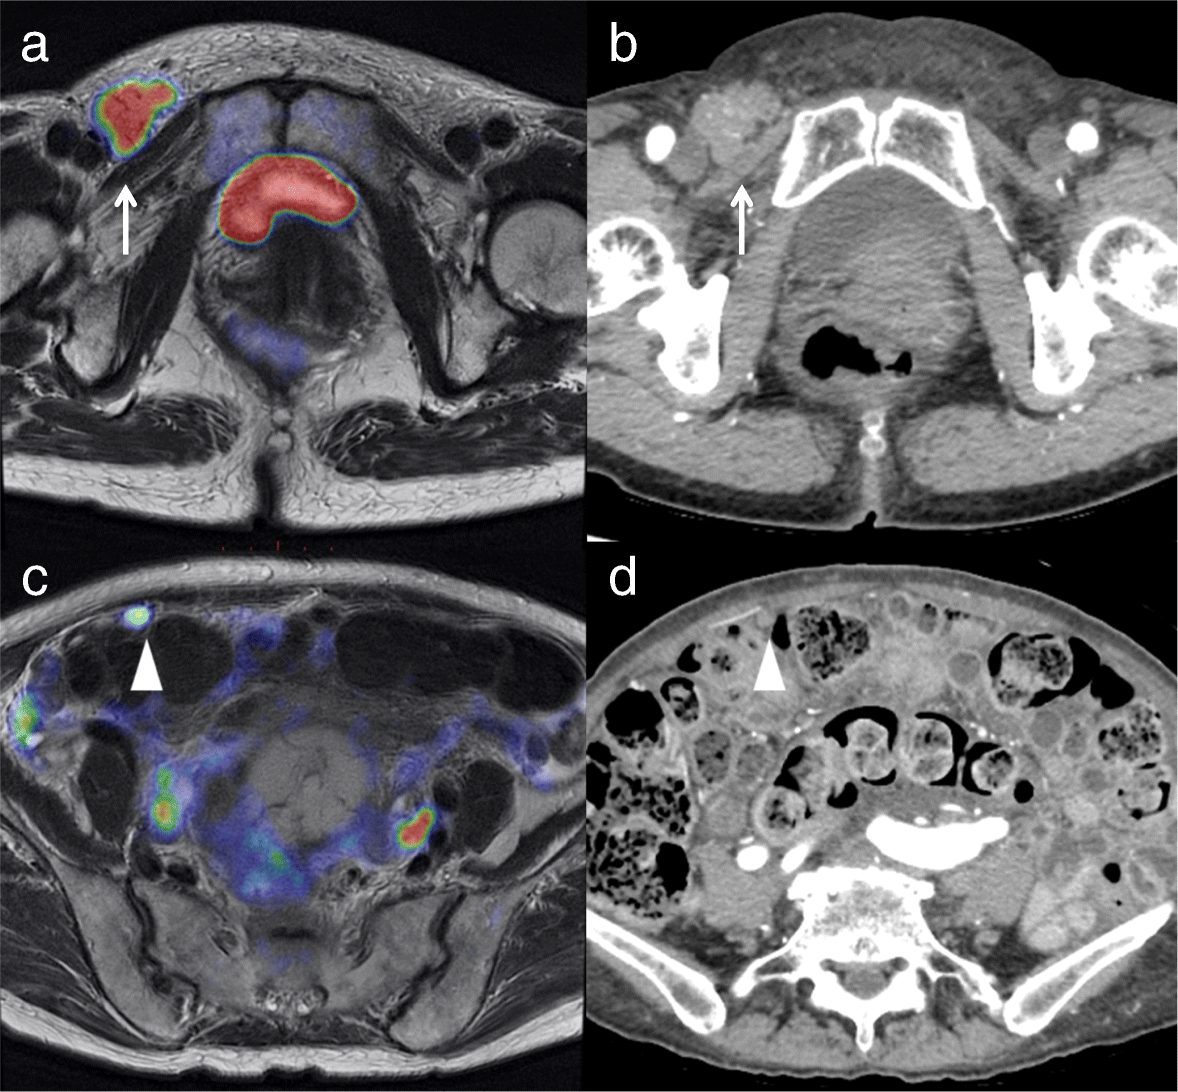

A 68-year-old woman with endometrial cancer and metastasis to an inguinal lymph node and the omentum (M1). a. Axial T2-weighted PET/MRI shows swelling of the right inguinal lymph node and high FDG uptake (arrow). b. The diameter of the node is > 10 mm (arrow) on contrast-enhanced CT. c. Axial T2-weighted PET/MRI shows omental dissemination with high FDG uptake (arrowhead) d. The diameter of the omental dissemination is > 10 mm (arrowhead) on contrast-enhanced CT. Histopathologic examination confirmed cancer involvement in the lymph node and omental nodule